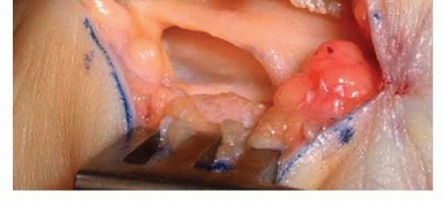

FIG 2 • CORTISONE INJECTION.

Wrist splints can be introduced.The physician can recommend or prescribe nonsteroidal anti-inflammatory drugs (NSAIDs). Corticosteroid injection into the carpal canal can be considered (FIG 2).Temporary relief from such an injection indicates that surgical decompression is likely to be successful.Hand therapy can be considered.Evidence suggests oral vitamin B12 or B6 treatments can be helpful.17,18